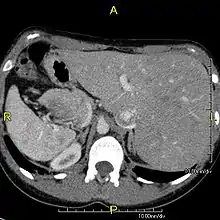

وُجِد الانعكاس الجذعي في حوالي 0.01% من البشر،[2] أو في حوالي شخص من كل 10,000. في الحالة الأكثر شيوعًا، الانعكاس الجذعي كليًا، يكون هناك تبديل كامل لجميع أعضاء البطن. لا يكون القلب في موضعه المعتاد أيسر الصدر ولكن على اليمين، وهي حالة تعرف باسم قلبٌ يمينيّ. ولأن العلاقة بين الأعضاء لا تتغير، فلا يعاني الأشخاص من أي أعراض أو مضاعفات طبية، على الرغم من وجوب تعريف وتحذير الطاقم الطبي في حالات الطوارئ من أن الأعضاء الداخلية للمريض منعكسة عن الوضع الطبيعي، على سبيل المثال للاستماع إلى ضربات القلب على اليمين وليس الجانب الأيسر من الصدر.[3]

التأثير على التشريح

تؤثر الحالة على جميع التراكيب الرئيسية داخل الصدر والبطن. إذ تكون الأعضاء منقولة عبر المستوى السهمي. يقع القلب على الجانب الأيمن من الصدر، والمعدة والطحال على الجانب الأيمن من البطن بينما الكبد والمرارة على الجانب الأيسر. يتواجد الأذين الأيمن الطبيعي في القلب على اليسار، والأذين الأيسر على اليمين. يُعكس تشريح الرئة فيكون للرئة اليسرى ثلاثة فصوص في حين للرئة اليمنى اثنان من الفصوص. تنعكس الأمعاء وغيرها من التراكيب الداخلية والأوعية الدموية والأعصاب واللمفاويات أيضًا.

إذا انعكس القلب إلى الجانب الأيمن من الصدر، فإنه يعرف باسم "الانعكاس الجذعي مع قلب يميني" أو "الانعكاس الجذعي الكُلِّي". إذا بقى القلب على الجانب الأيسر الطبيعي من الصدر، وهي حالة نادرة جدًا (1 من كل 2,000,000 شخص)، فإنه يعرف باسم "الانعكاس الجذعي مع أيسريَّة القلب" أو "الانعكاس الجذعي غير الكُلِّي".